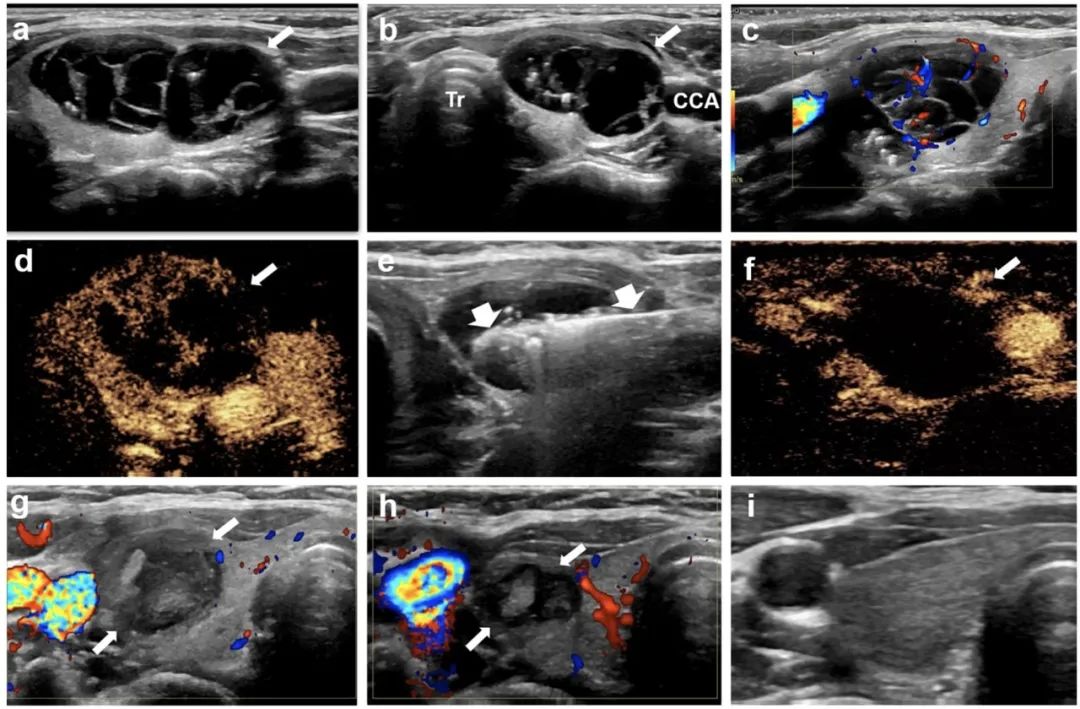

甲状腺右叶囊性为主结节,微波消融后3年,病灶完全消失